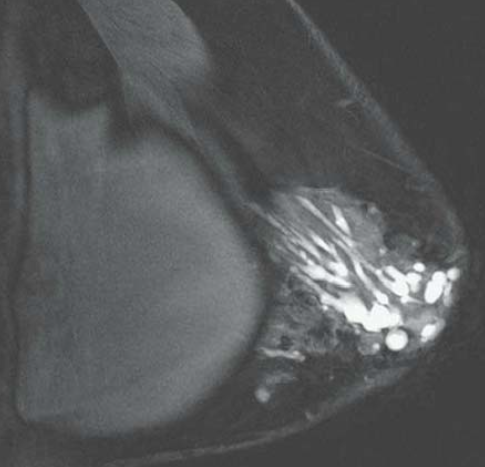

IRM

- Spontanément hyper T1

- Prise de contraste (partie inflammatoire des canaux)